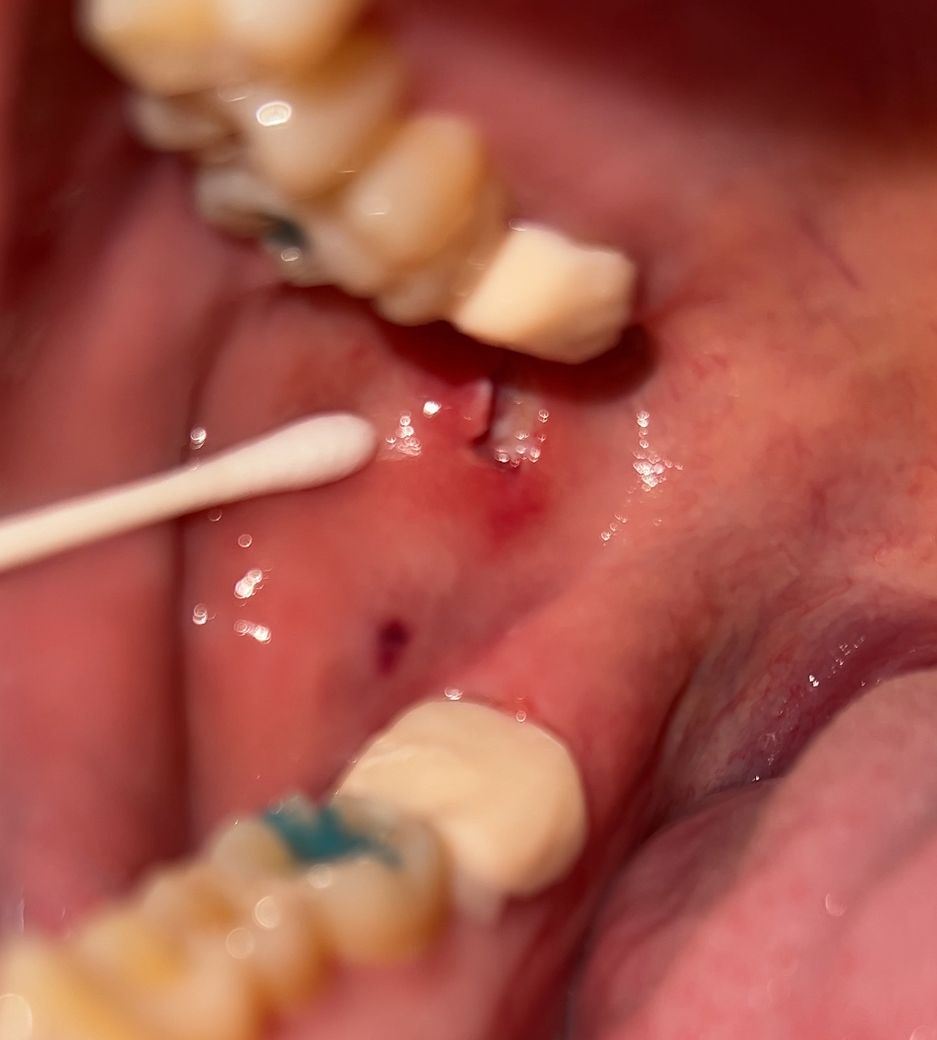

충치치료받은 첫날입니다 임시크라운 씌우기 전 충치 갈 때 볼쪽이 살짝 아팠는데 다하고 나와서 살짝 상처냈다고 하시길래 거울 보니 이렇게 파였는데 꼬메야될정도일까요..? 반대쪽도 크라운 해야되는데 무서워요ㅠ

꼬맬정도의 상처는 아닌것으로 보이며 시간이 지나게 되면 아물게 됩니다. 해당부위 염증이 덧나지 않도록 헥사메딘 가글액으로 가글하여 관리하고 맵고 짜고 신 자극감이 가는 음식은 아물때까지는 피하길 권합니다.

사진이라서 명확한 판단은 어렵지만 꼬매지 않더라도 회복될 겁니다.

잇몸의 회복은 빠른 편이기 때문에 약 2주정도 지나면 눈에 띄게 나을겁니다.

현재 사진 정도로는 꼭 꿰매지 않아도 됩니다. 물론 꿰매면 회복 정도는 빠르겠지만 지금 정도의 회복 패턴이라면 그대로 두면 시간이 지난 이후에 정상적으로 연조직이 회복됩니다. 맨 뒤에 치아를 치료할 때 지금과 같은 상처는 자주 나타납니다.

안녕하세요 치과의사 김철진입니다. 저정도 상처는 통증이 잇긴하긴하겟지만, 시간이 지나면 괜찮아 지실꺼에요. 꼬메지는 않으셔도 될것같습니다.

치아를 삭제하는 도중에 도구로 인해서 올해 연조직에 상처가 많이 생긴 것으로 보입니다 해당 부위를 봉합을 해 준다면 불편감이 더 줄어들고 치유가 빨라질 수 있을 것으로 생각됩니다 자세한 확인을 위해서 치과에서 진료를 받아 보는 것을 권유드립니다